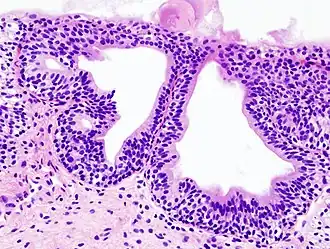

![]() Analiza histopatologică a unei cistite granulare, în urma unei biopsii. Colorație cu hematoxilină și eozină. | |